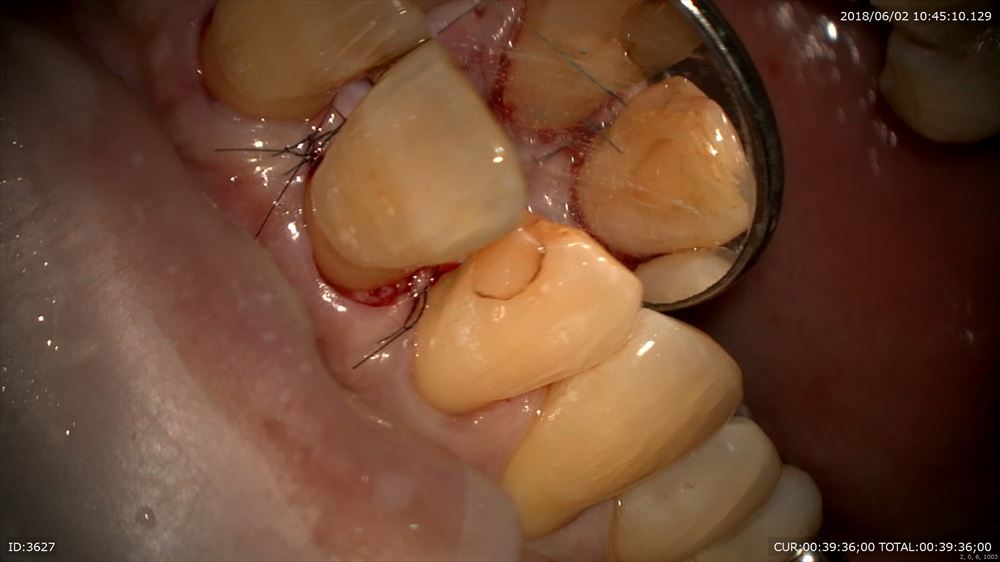

そこで歯周外科手術と言って歯茎を少しめくりデブライドメントをしていき治癒に向かわせます。

歯周外科手術に至っても昔はばっさり切っていました。

しかし現在はマイクロスコープ下で専用の器具と縫合時も髪の毛より細い糸で縫合しますので痛みはほぼありません。本当に患者さまは喜んで頂けます。

モディファイドウィッドマン手術終了後。

出血一切なし。